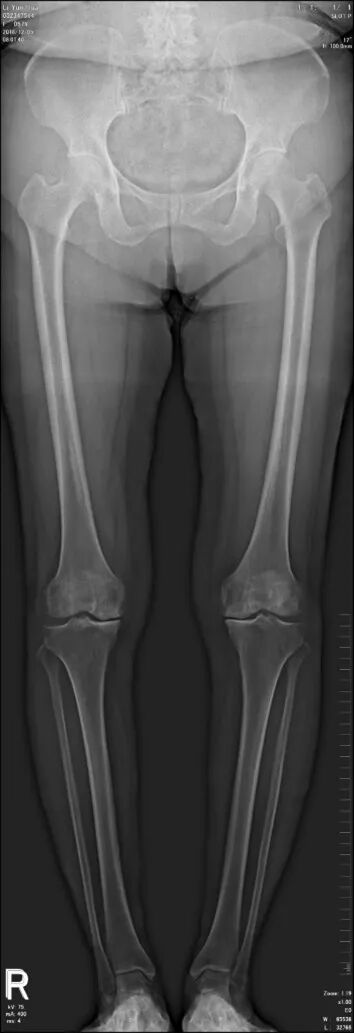

SLOT 的下肢图像

经 SLOT 功能生成的图像清晰度高,能够清晰显示股骨、胫骨的形态特征及关节间隙情况,确保测量数据的精准性。同时,其检查流程高效,可缩短患者体位保持时间,提升舒适度;且辐射剂量较低,符合临床安全标准。SLOT 功能的应用,使下肢全长检查更为高效、精准,为骨骼疾病的诊断及治疗方案的制定提供了可靠的影像学依据。